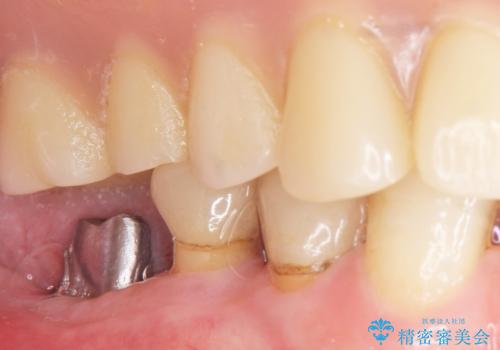

奥歯のインプラント 70代男性

患者様のご希望により、抜歯後インプラント治療を行いました。

- ¥550,000 (インプラント、骨増生、アバットメント、クラウン) ※税込費用は治療当時の料金となります

奥歯でしっかりと咬むことができるようになり、大変喜んで頂けました。

クラウンの種類:オールセラミッククラウン スタンダード